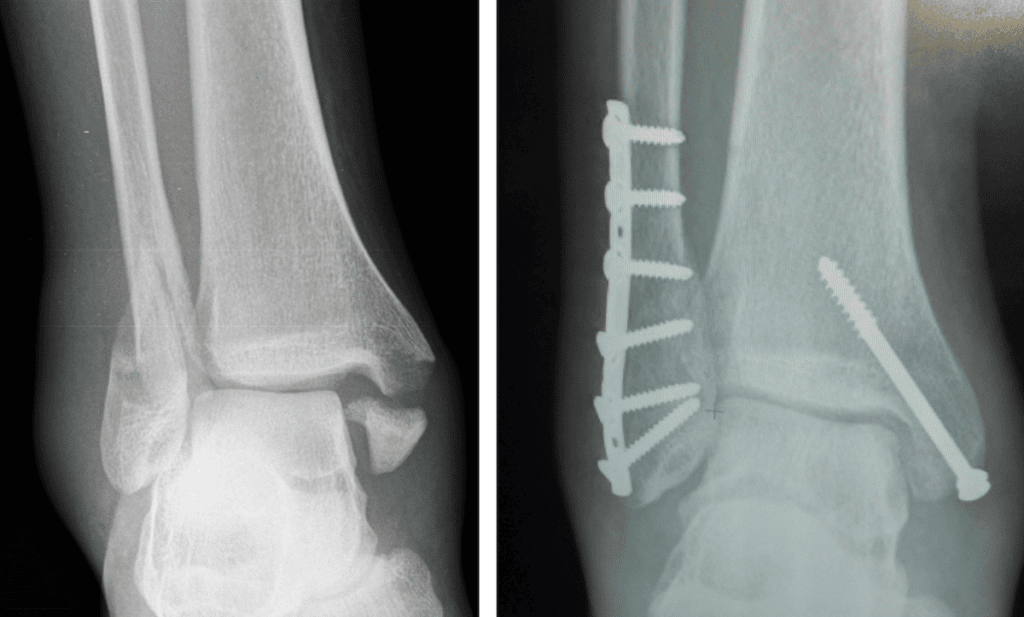

I am a 66 yr old C-7 SCI manual wheelchair user with 35+yrs post motorcycle accident. The last few years I have broken bones in both legs. The last injury happened in May 2024 when I fell transferring from wheelchair into my driver’s seat. I destroyed my left leg, breaking the femur, tibia and shattered my knee cap. Because of my lack of bone density the surgeon said he could not operate using screws or plates. He wanted to amputate above the knee. I had to teach him just because I don’t use my legs to walk I still use them to help in transfers. Explaining how I lift with my arms and then pivot on my legs during transfer made him decide on a Plan B. I would have to live with a non-union leg, meaning the femur is no longer connected to the knee. I immobilized the leg for 8 weeks then moved to a hinged brace permanently. Obviously it is not ideal, but is better than the alternative.